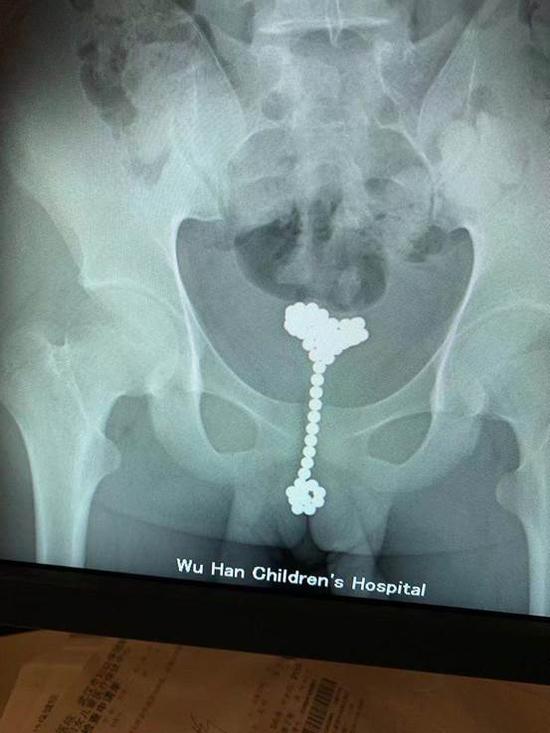

江华被紧急送往武汉儿童医院,当晚11时,泌尿外科主任医师王军接诊。当时,江华已经面色苍白、精神差、头晕呕吐,还有休克症状。王军主任为他连夜做了手术,凌晨取出两长串巴克球,江华这才转危为安。

李辰不好意思地承认,自己是为了“探索人体”,一时好奇才将珠子塞进去的,已经过去两个多月了。李辰随后被转到泌尿外科,王军主任手术取出了31颗巴克球。